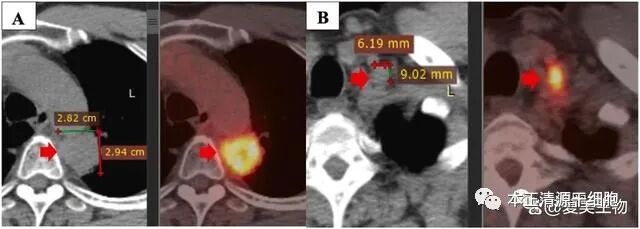

男性,时年60岁,诊断为NSCLC。无吸烟史、无咳嗽/背痛/乏力等症状。胸部CT显示左肺上叶25×31mm大小的原发肿瘤(下图A),伴纵膈淋巴结浸润。多发纵膈淋巴结肿大,最大者5×5mm。经穿刺活检和组织病理检查确定为肺腺癌,病理分期为T4N2M1a(IV期)。肿瘤标记物CA125轻微升高,CA199和CEA正常。基因检测未发现EGFR突变。由于病灶较大,且有纵膈浸润,手术不宜进行。

患者接受3个周期的一线治疗方案:卡铂+紫杉醇双药化疗,并在第三个周期联合放疗。治疗后PET/CT显示病灶缩小到12×7mm(上图B),取得部分缓解,肿瘤标志物回复正常,并改善了一些临床症状。

PET/CT复查显示局部进展,原发病灶大小增大为28×29mm,SUVmax值为11.2,并侵袭到纵膈胸膜和主动脉。此外,左侧锁骨上淋巴结新发转移灶,9×6mm(下图B)。